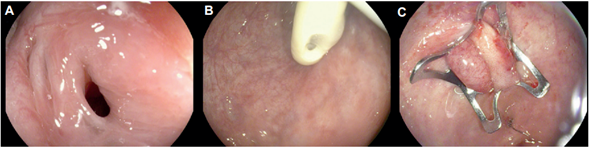

En el grupo de fístulas, la causa más frecuente fue la persistencia de la comunicación gastro-cutánea después del retiro de la sonda de gastrostomía. Las fístulas asociadas a crecimiento tumoral fueron 2, en las cuales no se pudo documentar éxito clínico. Otras 5 fístulas tenían antecedente de manejo quirúrgico para cáncer de estómago, próstata, colon y recto (Figura 3).

Figura. 3. A. Fistula rectovesical. B. Identificación de sonda vesical a través de fístula. C. Clip liberado con adecuado cierre de fístula (éxito técnico).